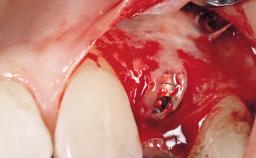

Late Flapless Placement of an Implant in a Maxillary Left Central Incisor Site

A 39-year-old male patient presented with a chief complaint of discomfort and gingival discoloration around his maxillary left central incisor. He was in good general health and was a non-smoker. His past dental history was significant because of the traumatic fracture of tooth 21 in a sporting accident at age 13. Initial dental treatment included endodontic therapy and a full-coverage restoration. The patient became symptomatic 5 years later, when structural failure of the tooth resulted in the dislodgment of the crown. Endodontic retreatment, apical surgery, and post-and-core restoration were performed.

Type of Implants One-Piece

Placement Protocol Early or late implant placement

Bone Volume Deficient horizontally, requiring prior grafting